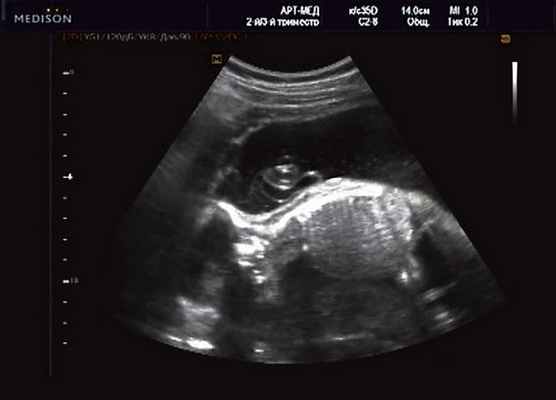

Беременная М., 21 года. Впервые обратилась в клинику в срок 20 нед беременности. Исследование проводилось на аппарате SonoAce-R7 (Samsung Medison) с использованием режима поверхностной объемной реконструкции 3D/4D. При изучении позвоночника плода в трех плоскостях костных деформаций не выявлено. В грудном отделе позвоночника обнаружено тонкостенное кистозное образование с анэхогенным содержимым, стебельчатой формы (рис. 10-12). Степень "прозрачности" содержимого была выше околоплодных вод, что позволяло идентифицировать его как ликвор. В проекции грыжевого выпячивания располагалась петля пуповины, дифференциальную диагностику которой без труда удалось провести с помощью ЦДК (рис. 13).

У плода наблюдалась выраженная гидроцефалия, обусловленная синдромом Аронольда - Киари II (рис. 14, 15).

Рис. 14. Беременность 20 нед. Гидроцефалия.

Рис. 15. Беременность 20 нед. Удлинение ножек мозга и вклинение мозжечка в затылочное отверстие при синдроме Арнольда - Киари II.

Учитывая типичную форму грыжевого выпячивания и отсутствие элементов нервной ткани, было высказано предположение о наличии у плода менингоцеле (рис. 16). Женщина приняла решение о прерывании беременности.

Рис. 16. Беременность 20 нед. Менингоцеле размером 37х21 мм.